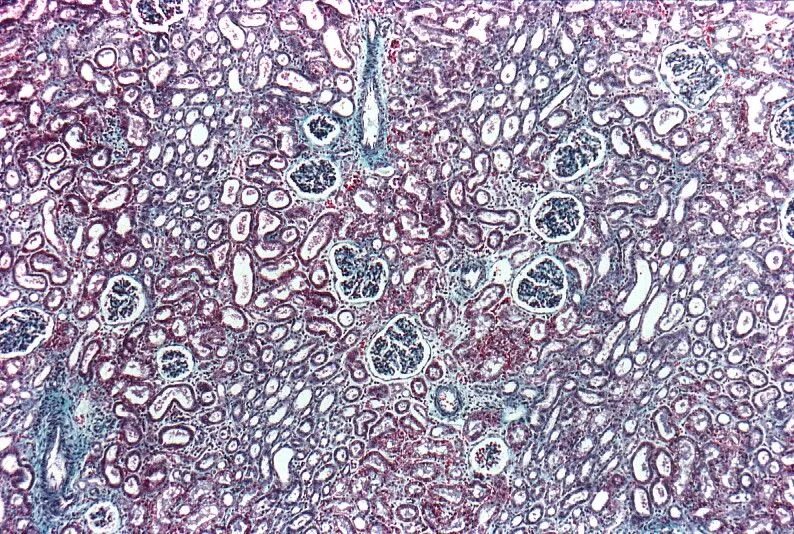

Гистохимия это